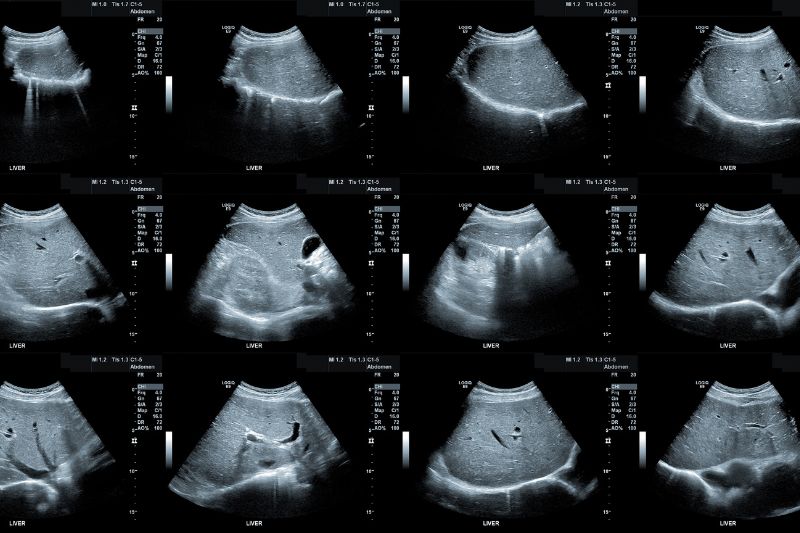

Za ultrazvok je že vsak sigurno slišal, mogoče ste že bili na kakšnem ultrazvoku, posebej mamice vemo kaj to pomeni. Ultrazvok trebuha ni nič drugače, kot drugi ultrazvoki. Kot sem že omenila, postopek ne boli, saj ti nič posebnega oziroma bolečega ne delajo. Edino moraš biti na ultrazvok trebuha na tešče in to najmanj 6 ur. Tudi pol litre vode vsaj eno uro pred samim posegom je dobro spit in to vodo obdržati v samem mehurju. Saj preden vas bo zdravnik poslal na ultrazvok trebuha vam bo dal vsa navodila, vam bo lepo vse razložil. Če bo vas kaj posebej zanimalo ga kar vprašajte. Moške je rado strah kakšnih posegov, saj vemo, da so oni tisti, ki slabo prenašajo bolečine. Ne rabite se bat, ultrazvok vas ne bo bolel, prav prijetno je, ko vam na trebuh stisnejo nekakšen gel in nato grejo po vašem trebuhu s s posebno napravo. Takoj poleg ima zdravnik računalnik, kjer takoj vidi kaj je težava v vašem trebuhu.

Med samim posegom oziroma ultrazvokom ležimo na hrbtu ali boku in smo čim bolj sproščeni. Ker trebuh zavzema kar velik del, mora zdravnik res dobro vse organe pregledat, da vidi kje tišči težava oziroma bolečina. Zato je odvisno od vsakega pacienta ali bolnika kako dolgo poteka sam postopek. Tudi takoj greste po samem posegu domov. Zdravnik bo dobil izvide, da vas bo kasneje oziroma takoj začel pravilno zdravit.